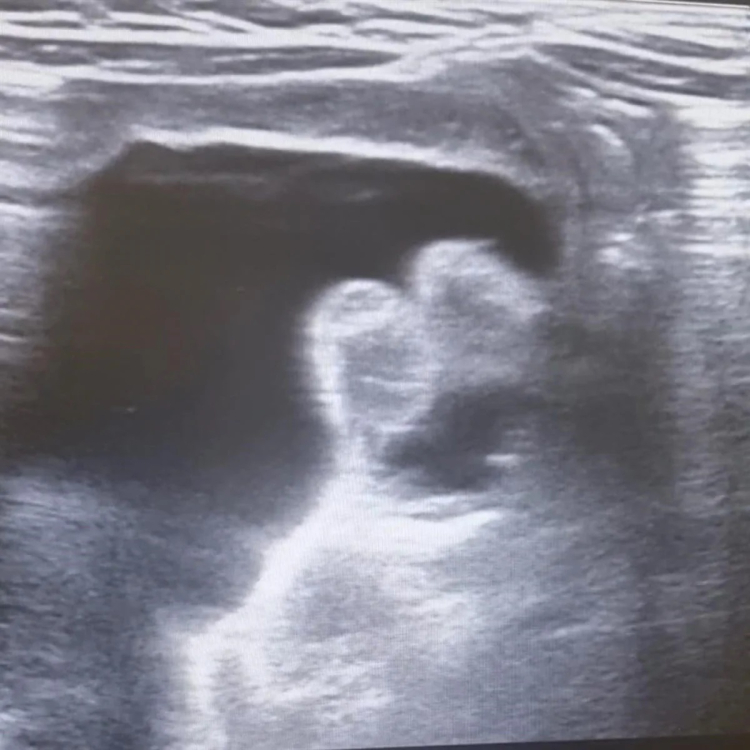

Çorum’da ilk kez bağırsak düğümlenmesi sebebiyle hastaneye kaldırılan 9 aylık çocuk ameliyatsız tedavi yöntemiyle sağlığına kavuştu.

Kanlı ishal ve genel durum bozukluğu nedeniyle Hitit Üniversitesi Erol Olçok Eğitim ve Araştırma Hastanesi’ne kaldırılan 9 aylık bebeğe halk arasında "bağırsak düğümlenmesi’’ olarak bilinen invajinasyon tanısı konuldu.

Yapılan değerlendirmeler neticesinde invajinasyonun düzeltilmesi için transrektal yoldan işlem yapılması kararı alındı.

Radyoloji Kliniği Eğitim Görevlisi ve Çocuk Radyolojisi Uzmanı Doç. Dr. Altan Güneş ve Çocuk Cerrahisi Kliniği Eğitim Görevlisi Prof. Dr. Çağatay Evrim Afşarlar tarafından acil serviste bebeğin düğümlenen bağırsağı ameliyata ihtiyaç kalmadan tedavi edildi.

İnvajinasyon veya halk arasındaki adıyla barsak düğümlenmesi, çocuk hastalarda sık görülen, erken tanı ve tedavi gerektiren, genellikle kanlı ishal, karın ağrısı ve genel durum bozukluğu gibi şikayetlerle hastaneye başvuru sebebi olan, tedavi edilmediği takdirde barsak delinmesi, barsak kaybı ve ağır vakalarda ölüme kadar gidebilecek ciddi bir acil durumdur.

Tedavisinde ameliyata alternatif seçeneklerden birisi olarak ultrasonografi eşliğinde redüksiyon seçkin merkezlerde uygulanan bir tedavi yöntemidir. Bu sayede hastaların hastanede kalış süresi azalmakta, hastalar cerrahi yöntemlerin olumsuz yan etkilerinden korunmakta ve hızla, bazen aynı gün iyileşebilmektedirler.